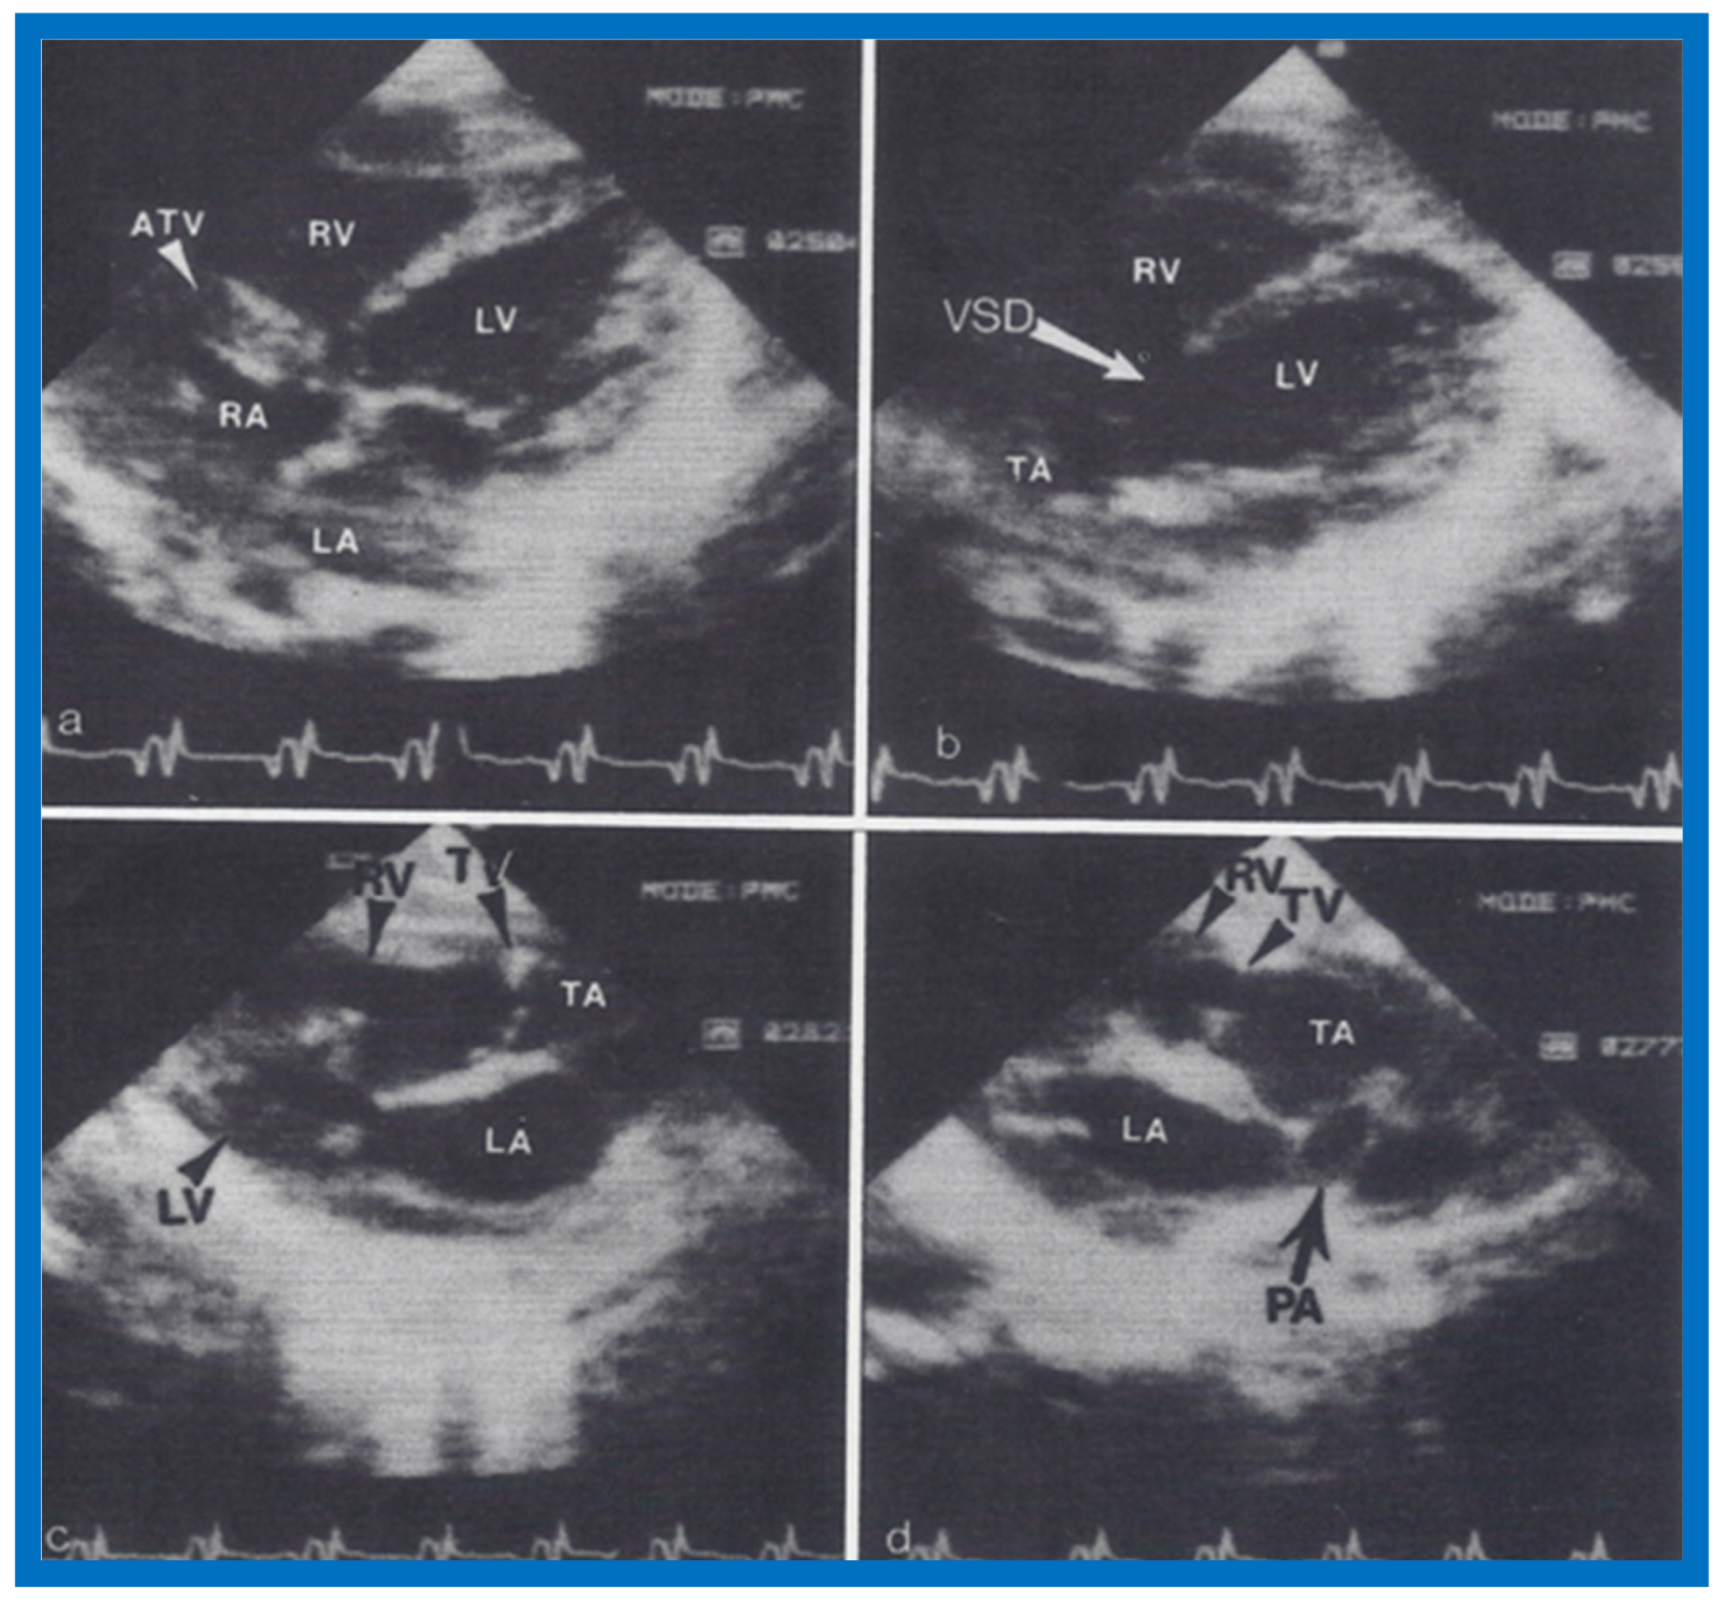

6. Echocardiographic Features of Tricuspid Atresia

The M-mode and two-dimensional echocardiographic features of tricuspid atresia were discussed in the author’s first book on tricuspid atresia, written in collaboration with his colleague, Dr Wesley Covitz at the Medical College of Georgia [7]. The two-dimensional (2D) echocardiographic pictures in 1982 were crude (Figure 14) [7]; however, they represented the state of the art echocardiography machines of that time.

Figure 14.

Selected video frames from apical four-chamber view of a two-dimensional (2-D) echocardiographic study demonstrating dense band of echoes between the right atrium (RA) and hypoplastic right ventricle (RV). Line drawings are shown beneath the 2D frames. Note that the mitral valve is closed in the left image while it is open in the right image. The atretic tricuspid valve echoes remain unchanged. LA, left atrium; LV, left ventricle. Reproduced from Covitz W., Rao P.S. [7].

Figure 15.

Selected video frames from subcostal four-chamber view of a two-dimensional (2-D) echocardiographic study demonstrating atretic tricuspid valve (ATV) (thick arrow), represented by a dense band of echoes between the right atrium (RA) and hypoplastic right ventricle (RV). In (A), the mitral valve (MV) is closed, while in (B), it is open. Note the improvement from the pictures shown in Figure 14. LA, left atrium; LV, left ventricle. Reproduced from Rao P.S. [35].

Figure 16.

Apical four-chamber view pictures of another infant with tricuspid atresia (large arrows in A,B) with ostium primum atrial septal defect (slanted arrow in B). Note small right ventricle (RV) and a ventricular septal defect (small arrows in A and B). LA, left atrium; LV, left ventricle; RA, right atrium. Reproduced from Covitz W., Rao P.S. [36].

More recently, the author reviewed the echo-Doppler evaluation of tricuspid atresia [37,38,39]; these findings will be presented. M-mode echocardiography, while not diagnostic, is useful for evaluating the size of the left atrium (LA) and left ventricle (LV) and LV function. On 2D echocardiography, the atretic tricuspid valve is visualized directly as a dense band of echoes at the site where the tricuspid valve should be in the most frequent muscular type, as shown in Figure 14, Figure 15, Figure 16 and Figure 17. This anatomy is better demonstrated in apical and subcostal four-chamber views than in other views. The other types, namely membranous, valvular, Ebstein’s, atrioventricular septal and unguarded valve with muscular shelf (Figure 18) [40], are rare and may also be recognized on 2D echocardiography.

Figure 17.

Selected video frames from apical four-chamber, 2-dimensional echocardiographic views of a neonate with tricuspid atresia showing an enlarged left ventricle (LV), a small right ventricle (RV) and a dense band of echoes at the site where the tricuspid valve echo should be (ATV) (thick arrow) with closed (A) and open (B) mitral valve. A moderate sized ventricular septal defect (VSD) (thin arrows) is shown. LA, Left atrium; RA, Right atrium. Reproduced from Rao P.S. [39].

Figure 23.

Two-dimensional echocardiographic video frames demonstrating (a) atretic tricuspid valve (ATV) between the right atrium (RA) and right ventricle (RV), (b) a large subtruncal ventricular septal defect (VSD), (c) thickened and somewhat domed truncal valve (TV) leaflets, and (d) origin of the pulmonary artery (PA) from the posterior aspect of the truncus arteriosus (TA). LA, Left atrium; LV, left ventricle. Reproduced from Rao P.S., et al. [22].

Figure 24.

Video frame from a two-dimensional echocardiographic and color Doppler study demonstrating (A) atretic tricuspid valve (ATV) between the right atrium (RA) and right ventricle (RV) and blood flow from the left atrium (LA) into the left ventricle (LV) across the mitral valve. The RV (arrow) is very small and hypoplastic. (B) LV and RV with a large ventricular septal defect (VSD) below the truncus arteriosus (TA). Turbulent flow across the truncal valve suggests truncal valve stenosis. (C) origin of the pulmonary artery (PA) from the TA by color flow (arrow), and (D) division of right (RPA) and left (LPA) pulmonary arteries from the PA (labeled in d) in a short-axis view. TV, truncal valve leaflets. Reproduced from Rao P.S., et al. [22].